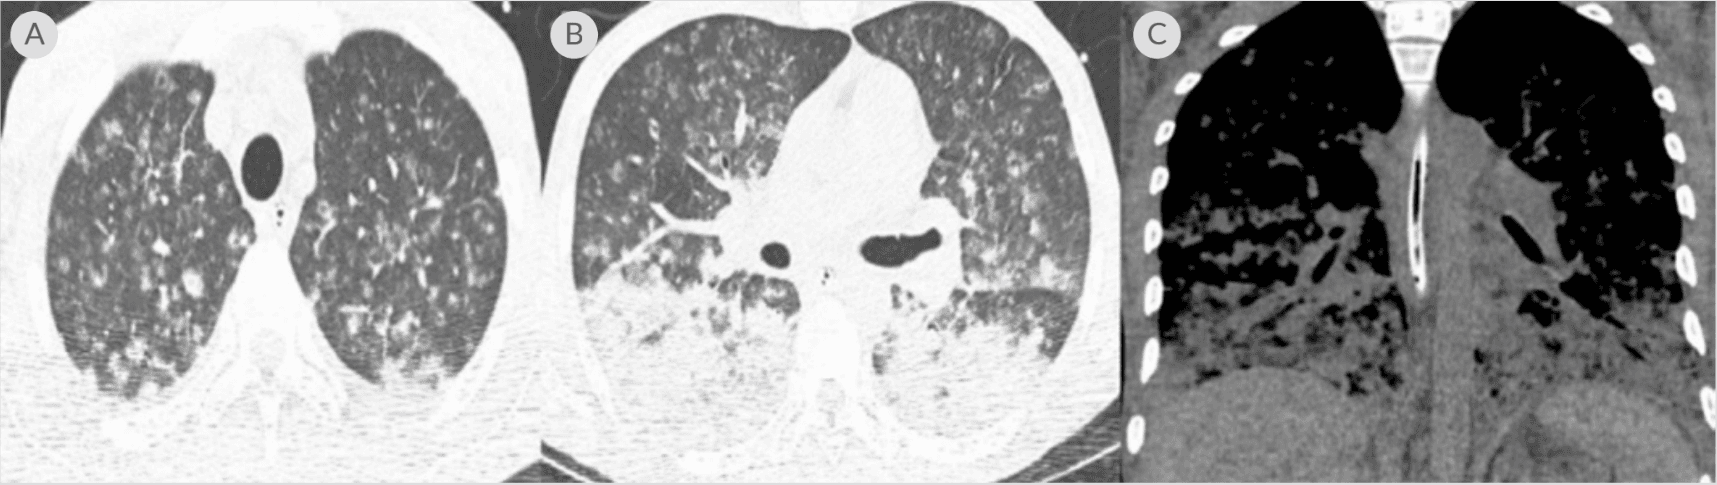

(A) CT chest axial lung window showing miliary changes in both lungs; (B) CT chest axial lung window showing several nodules with developing central cavitation and bilateral consolidation; (C) coronal window showing bibasilar airspace disease with confluent consolidation throughout the lung bases5

39 years old with untreated HIV infection and respiratory failure requiring mechanical ventilation with an unclear etiology.

Tests Performed: Diagnostic tests performed for evaluation of pneumonia and other etiologies included absolute CD4 count of 6, HIV viral load of 332,909 copies/ml, CMV IgG positive; CXR with bilateral multinodular changes, chest CT with miliary lesions, brain MRI with multiple ring enhancing lesions; negative testing included: blood and BAL cultures; VZV, syphilis, and tuberculosis studies; Histoplasma/ Aspergillus/ Legionella/ Cryptococcus/ Influenza antigens.

Karius Test Result: Toxoplasma gondii

Outcome: Started 6-week course of pyrimethamine/sulfadiazine, discontinued piperacillin/tazobactam; resulting in significant clinical improvement allowing the patient to be started on antiretroviral therapy.